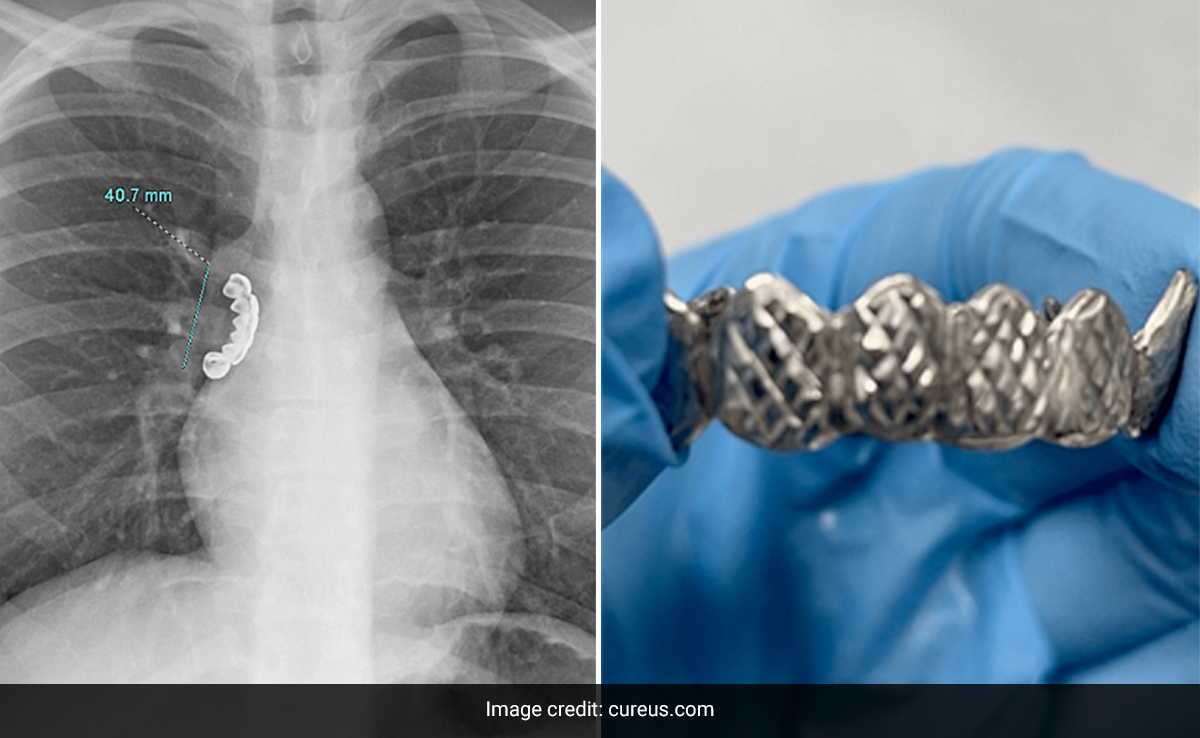

He was rushed to the hospital where an X-ray revealed he had a 4.1 cm denture stuck in the airway of his lung. A case study detailing the incident was published this week in the Cureus medical journal.

''A chest x-ray revealed a radiopaque foreign body measuring about 4.1 cm over the right main bronchus. The Foreign Body appeared to be horseshoe-shaped, with sharp and jagged edges resembling teeth. Bronchoscopy was performed to remove the inhaled foreign body. Despite traversing the vocal cords, retrieval was particularly challenging given the shape and size of the dental product. Unfortunately, the horseshoe-shaped object had sharp and jagged edges,'' the journal reads.